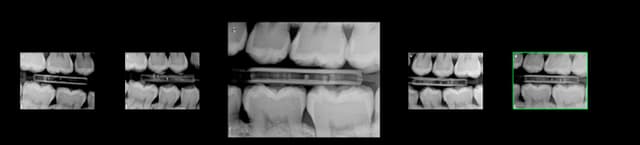

Exemple pratique, que peut on coter ici ?

Capture d e cran 2016 02 15 13.15 - Eugenol

> Exemple pratique, que peut on coter ici ?

Rien de rien...